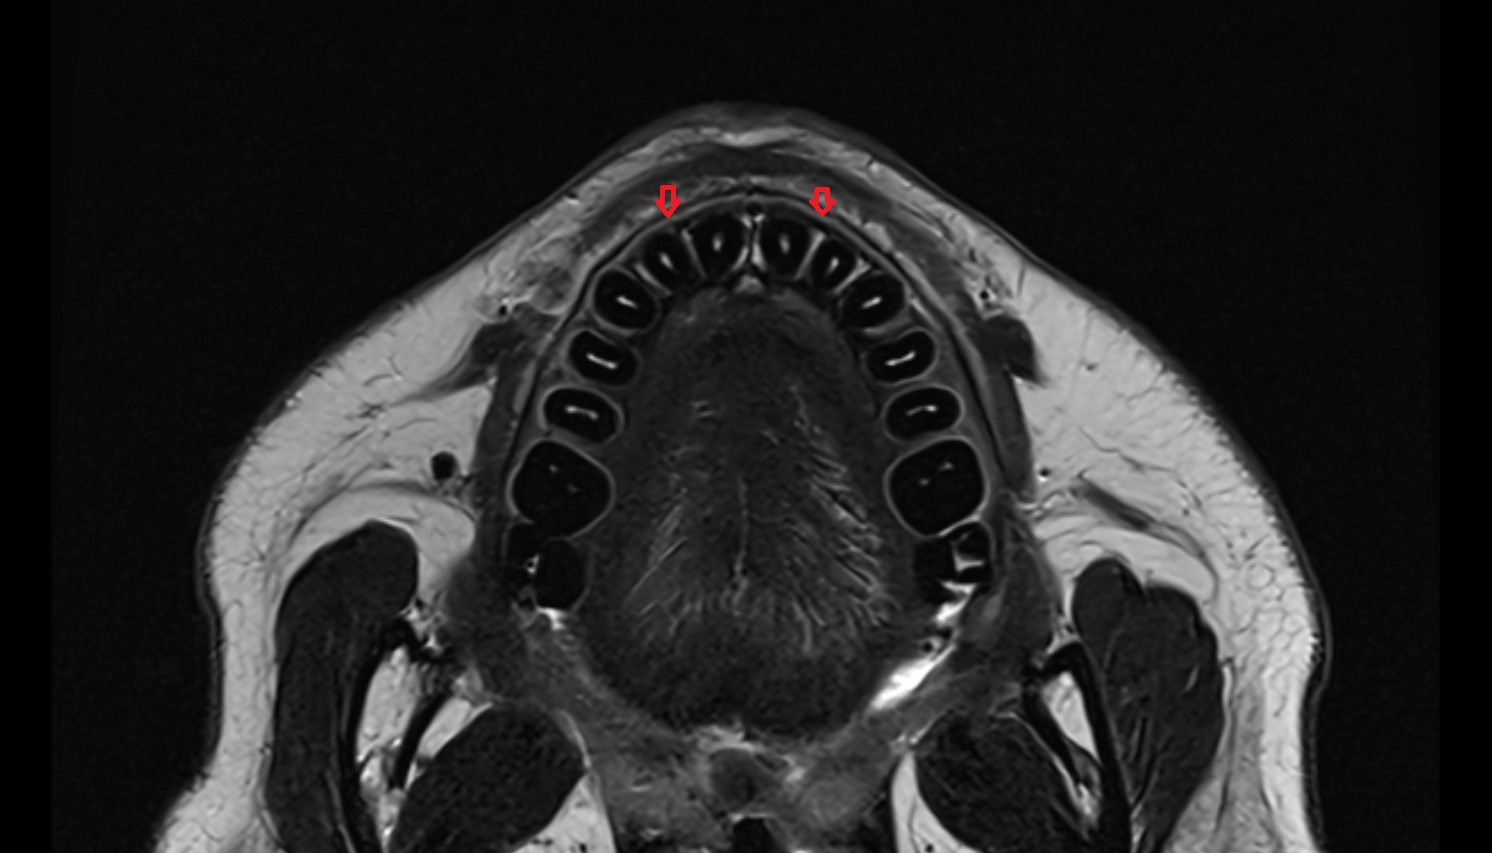

- Central inferior incisor tooth

- Central superior incisor tooth

- Inferior canine tooth

- Lateral inferior incisor tooth

- Lateral superior incisor tooth

- superior canine tooth

- Superior first molar tooth

- Superior first premolar tooth

- Superior second molar tooth

- Superior second premolar tooth

- Superior third molar tooth